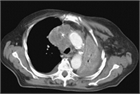

病態

1. 上大動脈症候群とは、上大静脈の閉塞や狭窄によって生じる上半身からの静脈血の還流障害により、静脈圧の上昇を来し、頭部、顔面、上肢、頚部および上半身のうっ血・浮腫を来す症候群である。

1. その原因として肺癌など胸部悪性疾患が多く、腫瘍に関連する救急疾患(Oncologic emergency)の1つに位置づけられている。